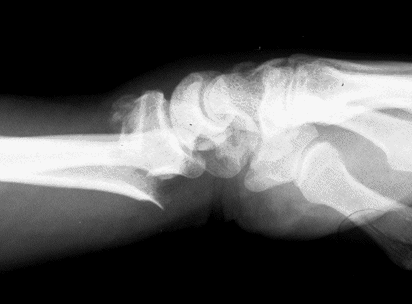

Case 3 Preop

Case3 Preop